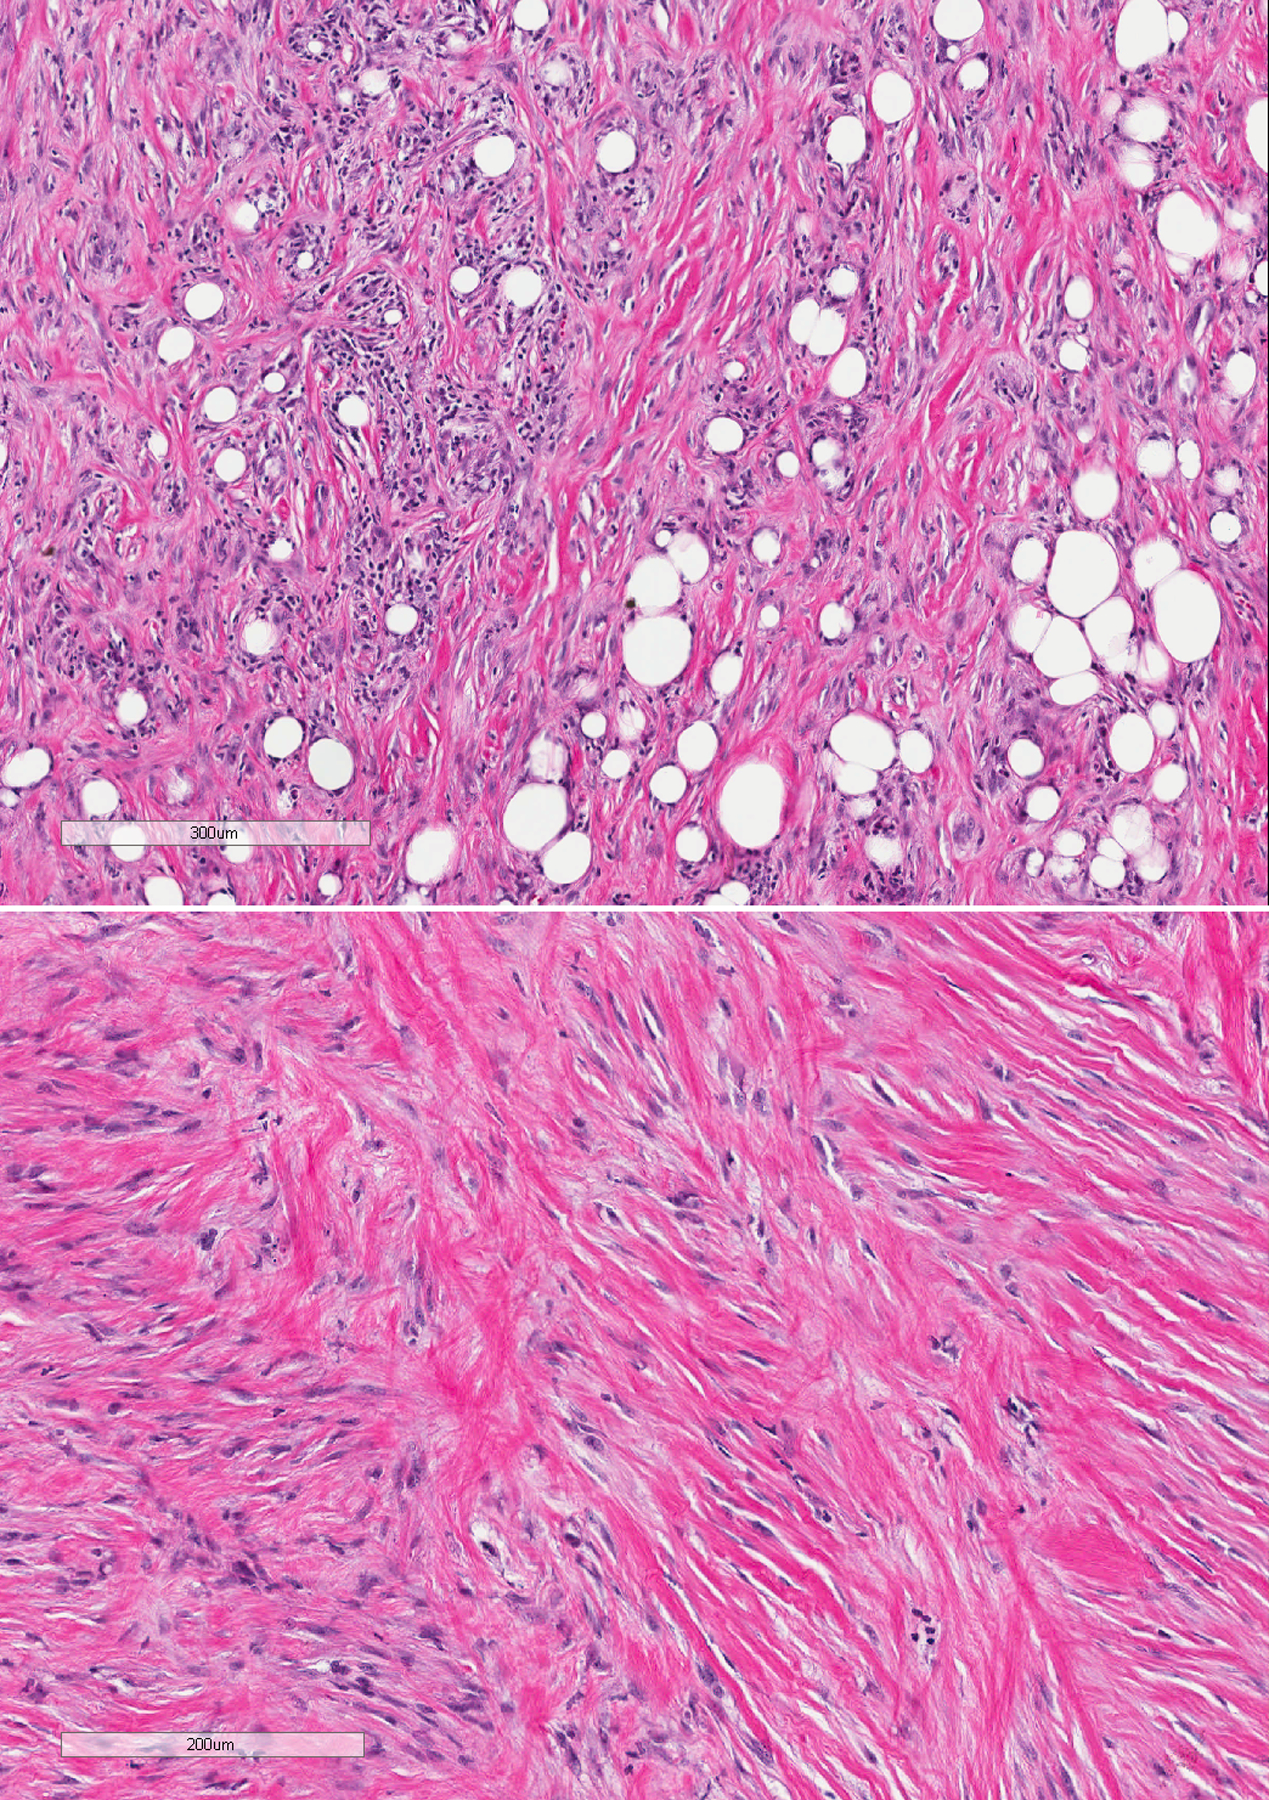

Sarcomatoid mesotheliomas can be challenging to diagnose on small biopsy specimens, where limited material may preclude definitive assessment of invasion and lesional cells can have relatively bland cytology with no mesothelial marker expression. We report a case of a patient who presented with a pleural effusion and had subsequent pleural biopsy that showed a bland, uniform spindle cell proliferation in a mildly myxoid background. There was little if any collagen; no chest wall, soft tissue, or fat; and mesothelial markers were negative. The cells were positive for pancytokeratin and GATA3 by immunohistochemistry, and in situ hybridization showed a "negative" result for homozygous loss of CDKN2A; however, there was partial (heterozygous) loss of one allele. A diagnosis of atypical spindle cell proliferation was made based on these findings. Several months later, the patient had a repeat pleural biopsy that showed spindled cells with more pleomorphism, areas of invasion into the chest wall, and the same partial loss of CDKN2A, consistent with a sarcomatoid mesothelioma. This case underscores the challenges present on small biopsy specimens, the fact that sarcomatoid mesotheliomas can be relatively bland appearing with focal pleomorphism, and that heterozygous loss of CDKN2A should be considered a positive result indicative of a neoplastic process.